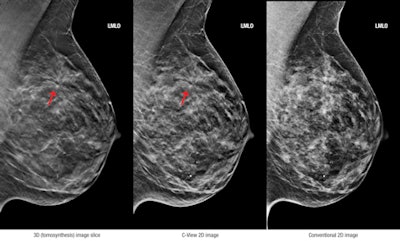

3D (tomosynthesis) image slice (left), C-View 2D image (center), and conventional 2D image (right). Images courtesy of Hologic.New tools also became available in 2013 that will improve the flexibility of tomosynthesis. Hologic, the first company to bring breast tomosynthesis to the U.S. market, received U.S. Food and Drug Administration (FDA) approval for a 2D mode that will enable its Selenia Dimensions 3D tomosynthesis systems to produce the conventional 2D mammography images that are typically used alongside the tomo volume when reading studies. The company also launched a 3D breast biopsy option designed to be used with its conventional and tomosynthesis mammography systems.